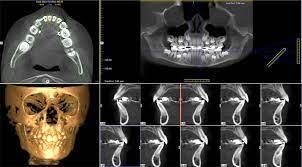

3 Boyutlu görüntüleme (Dental tomografi)

Dental tomografi, diş hekimliği uygulamalarında kullanılan yüksek çözünürlüklü üç boyutlu görüntüler elde etmek için kullanılan ileri radyolojik bir teknolojidir. Bu teknoloji, diş ve çene yapısının detaylı bir şekilde incelenmesini sağlayarak implant planlaması, çene cerrahisi ve diş kökü tedavileri gibi karmaşık işlemlerin daha hassas bir şekilde planlanmasına yardımcı olur. Özellikle implant cerrahilerinde altın standartta bir ileri görüntüleme yöntemidir. Dental tomografi, diş hekimlerine daha doğru teşhis koyma ve tedavi planlaması yapma imkânı sunarak hastalara daha etkili ve kişiselleştirilmiş bir ağız sağlığı hizmeti sunar.